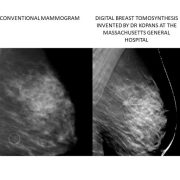

Dr. Kopans invented and led the team that developed Digital Breast Tomosynthesis which is replacing standard two-dimensional mammography and increasing our ability to detect more early cancers while at the same time, reducing the recall (“false positive”) rate.